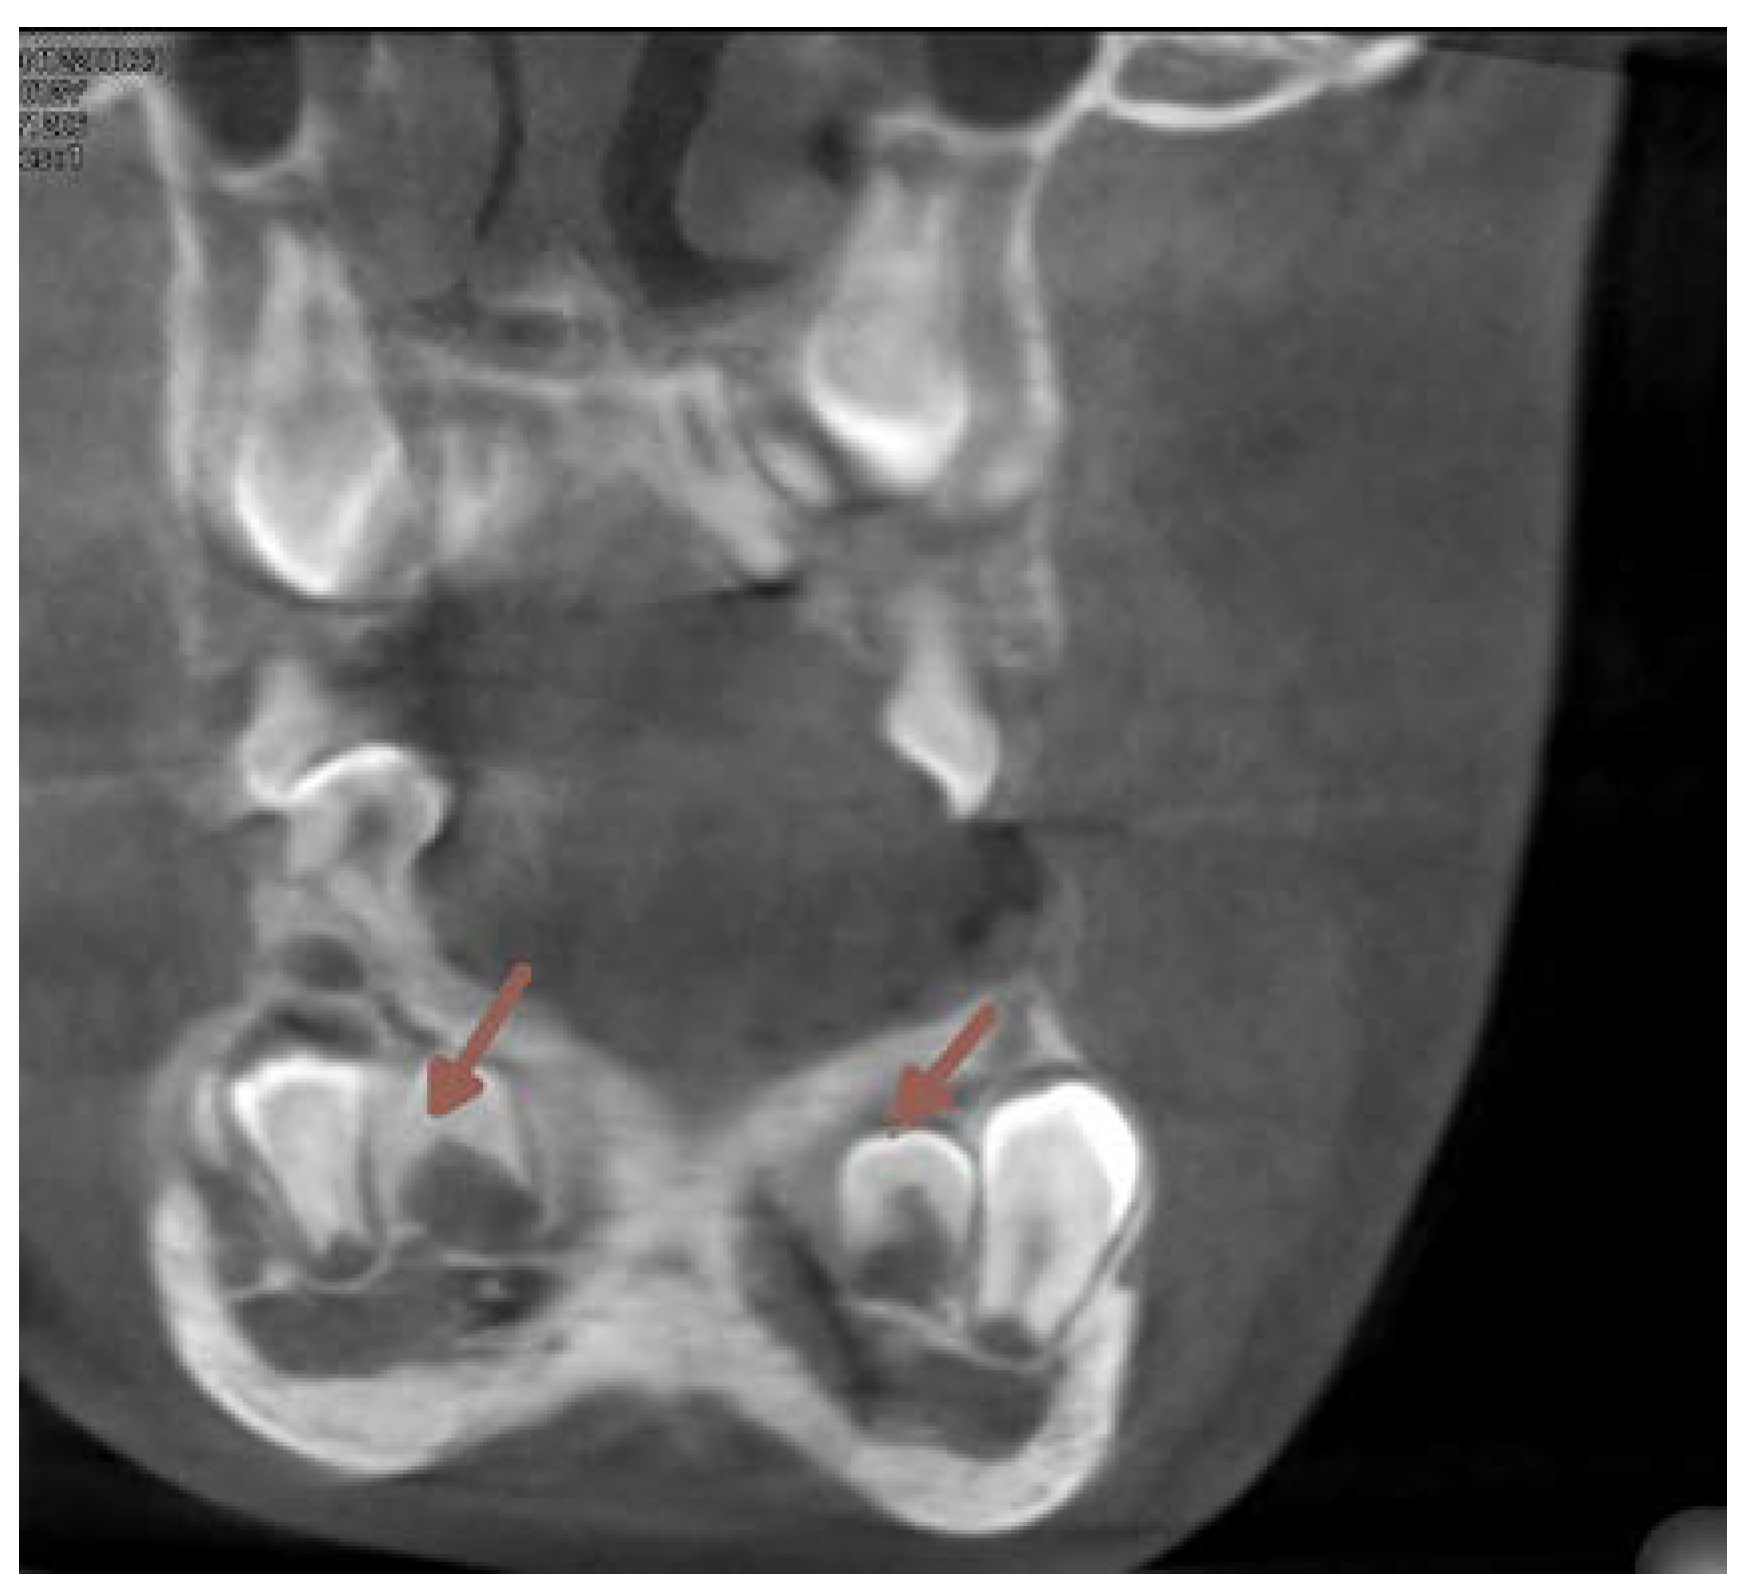

The next two OPG x-rays were taken after 11 months. On the latter (2017) (Figure 5) it became clear, that 22 and 11 were inhibited in eruption. ( DA 9,1 and 9,3, CA 12 y 11 mths) The patient was referred to the second CBCT scan image reproduction to make clear the underlying surgical situation. (Figure8). The CBCT scan revealed the position of supernumerary teeth also in the lower dental arch. (Figure 8.,9.)

Figure 8. CBCT vertical section perpendicular to the alveolar ridge on the level of the incisors. (2017).

At this time the 33 and 43 were slowing down their eruption, therefore another surgical intervention was needed. Another CBCT scan image was necessary to prove the proximity of the crowns of the lower canines to the apical area of the lower lateral incisors. (Figure 15).